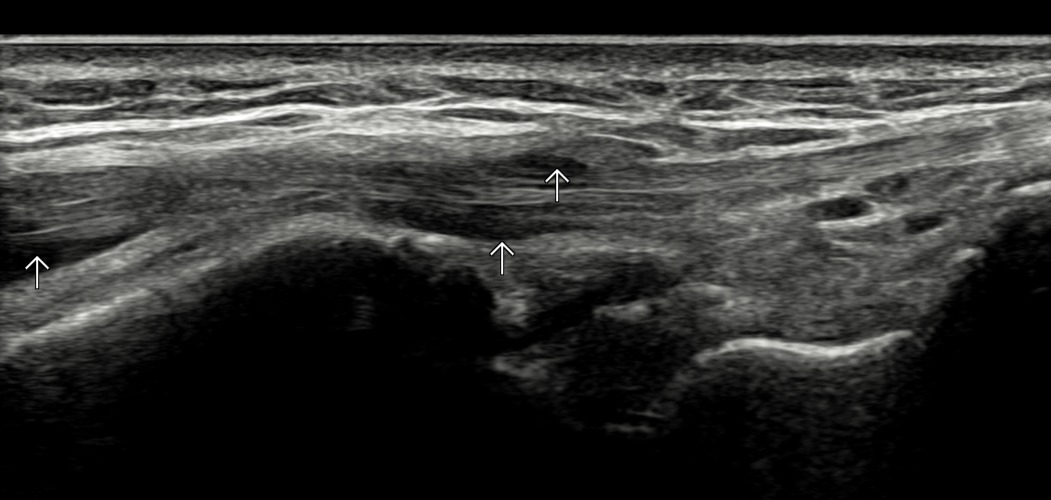

- 치료기간 : 25 . 4 . 25 ~ 25 . 6 . 25

- 치료횟수 : 1Cycle(5 회)